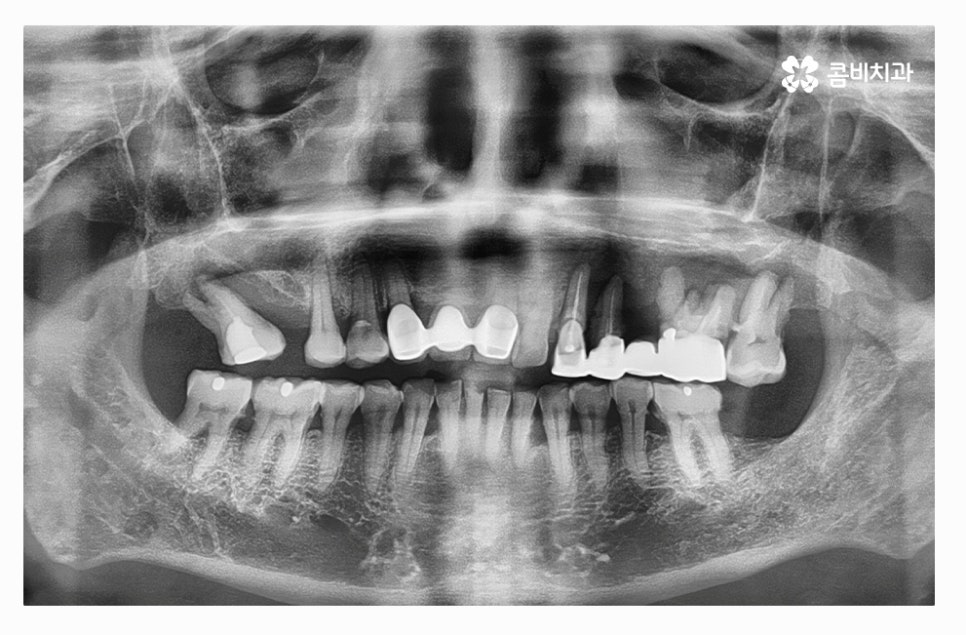

오늘 보여드릴 사례의 경우 치주질환과 염증으로 인해서 윗니를

모두 잃게 되어 전체임플란트 시술을 하게 된 사례라고 할 수 있는데요.

치주염이 심해지면 주변 잇몸까지 점점 안 좋아지다가

이번 사례처럼 한꺼번에 치아를 잃게 되는 상황이 발생할 수 있어요.

치아를 발치한 후 잇몸 뼈의 상태를 보면 잇몸이 내려앉아 있고

잇몸 뼈가 부족해진 상태라는 것을 알 수 있는데요.